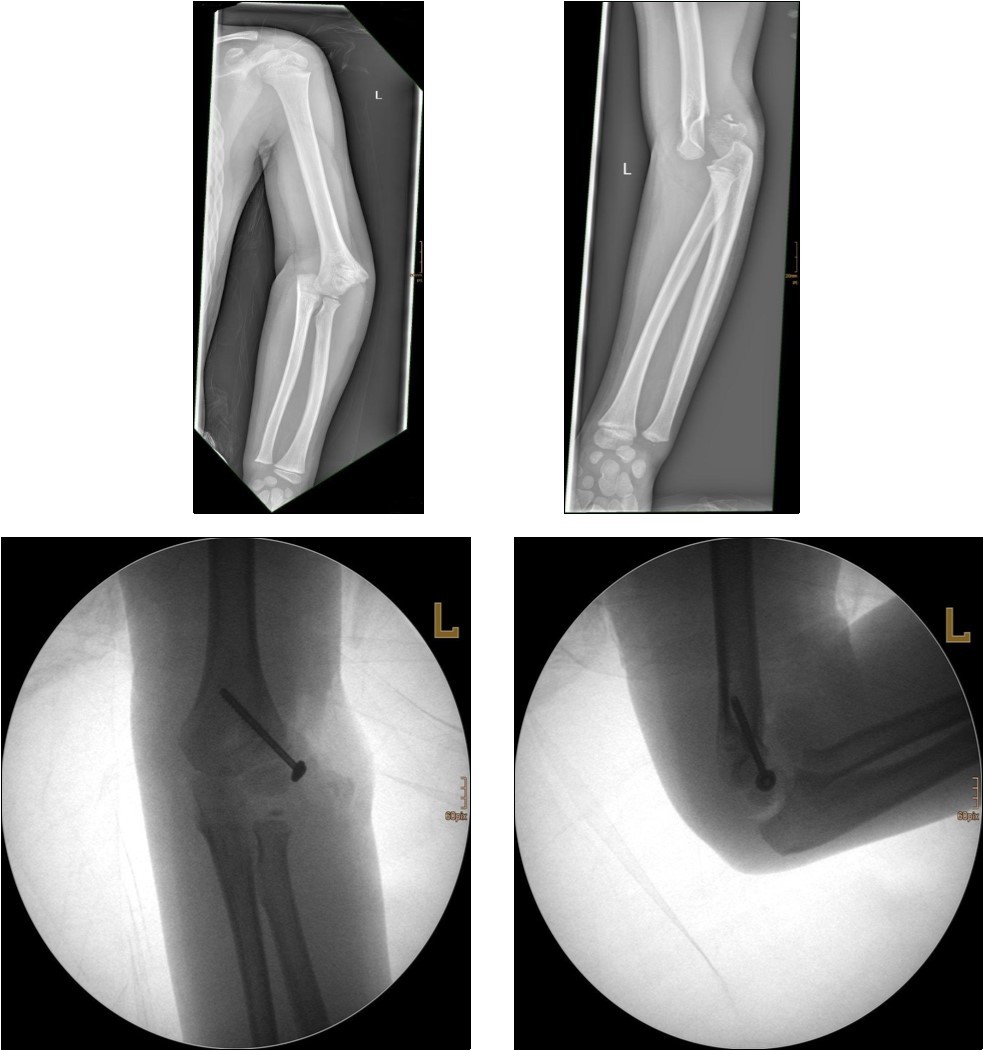

Non-displaced and stable fractures may be treated by cast immobilization with close follow-up, but fractures displaced >2 to 3 mm may indicate surgical fixation 7, 8. Surgical treatment can be done either by closed reduction and percutaneous osteosynthesis or open reduction and osteosynthesis. Figure 3.

Figure 3.9 year old male patient with a elbow dislocation and a dislocated left lateral condyle fracture which was treated by open reduction and osteosynthesis with a screw (personal collection)